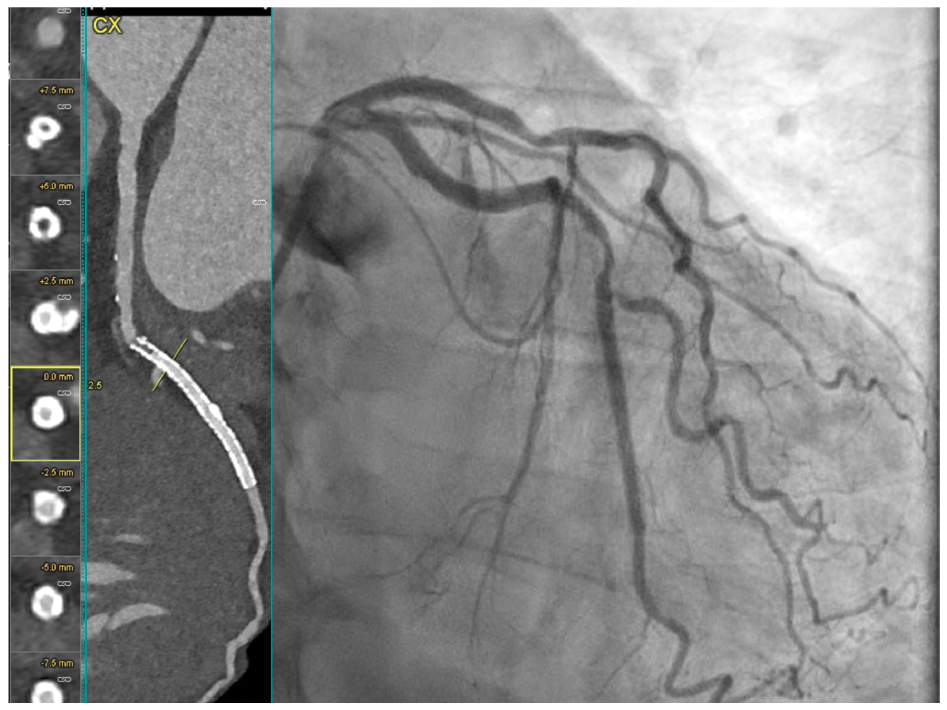

Using Photon-Counting CT to Image Stents in PCI Patients

Images/courtesy WellSpan Heart & Vascular Institute

In this case, a 73-year-old male with a remote PCI to the right coronary artery (RCA) and circumflex coronary artery (Cx), dyslipidemia, and hypertension presented with chest discomfort on exertion. A CCTA (Naeotom Alpha PCCT scanner, Siemens Healthineers) was performed to evaluate the patient’s symptoms. Sharper kernels with higher iterative reconstruction were used to facilitate stent visualization. The CCTA demonstrated complex calcified and noncalcified plaque in the mid-segment of the left anterior descending (LAD) coronary artery (Figure 1) with moderate stenosis.